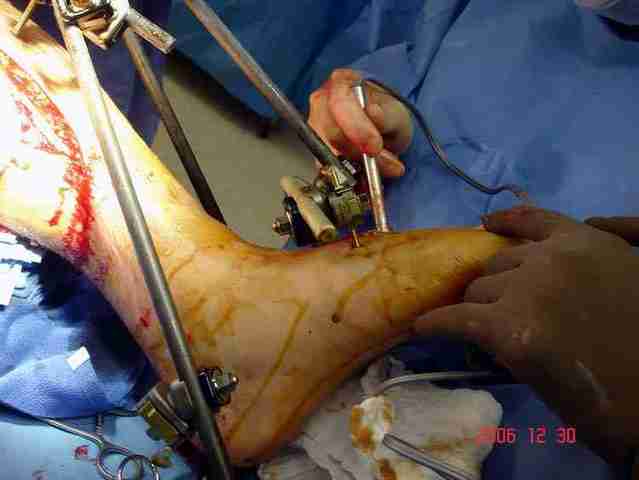

Срочная фасциотомия на всех 4 компартментах: латерально и медиально,

кстати было достаточно только латеральной фасциотомии, чтобы услышать на допплере пульсацию,

на бедре измерения не подтвердили подозрения на компартмент синдром и рана была закрыта вакуумной губкой (wound VAC).